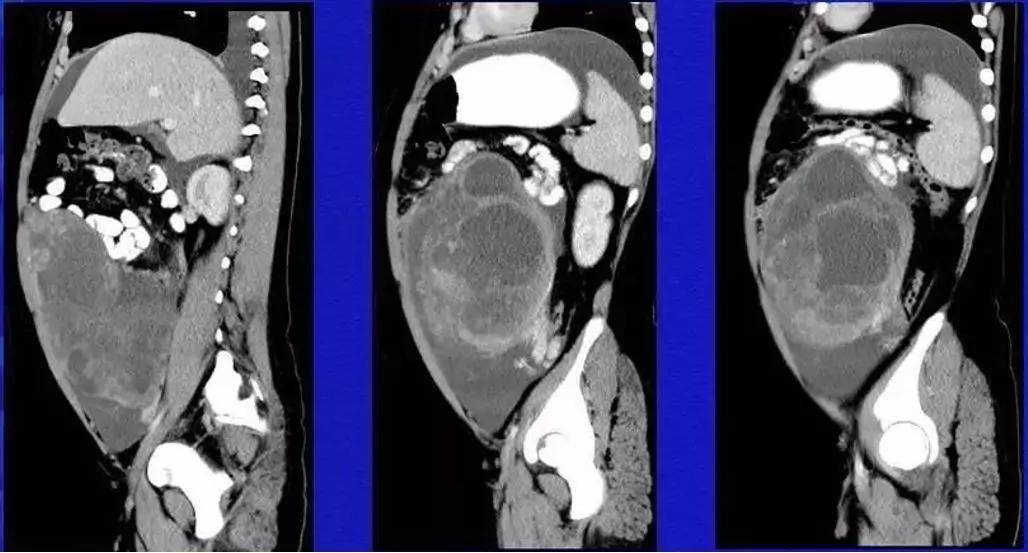

病理:浆液性囊腺癌

病理:颗粒细胞瘤

病理:子宫肌瘤粘液样变性